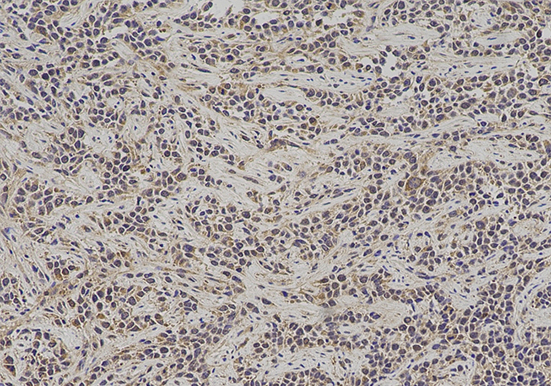

实验结果展示: